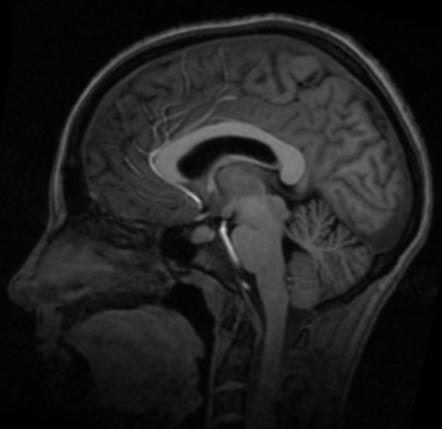

3. 测试结果

参考图像

浮动图像

配准图像